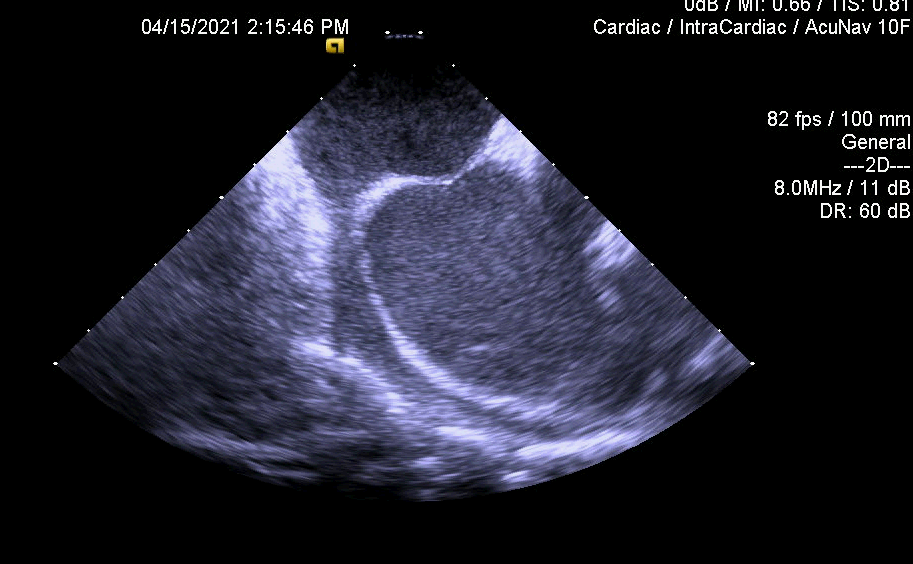

亮点1:心房永存左上腔房颤患者,ICE指导下房间隔穿刺

亮点2:ICE指导术中评估左心耳封堵情况

亮点3:ICE多维度评价左心耳封堵结果—锚定,有无露肩,压缩比测量,有无残余分流